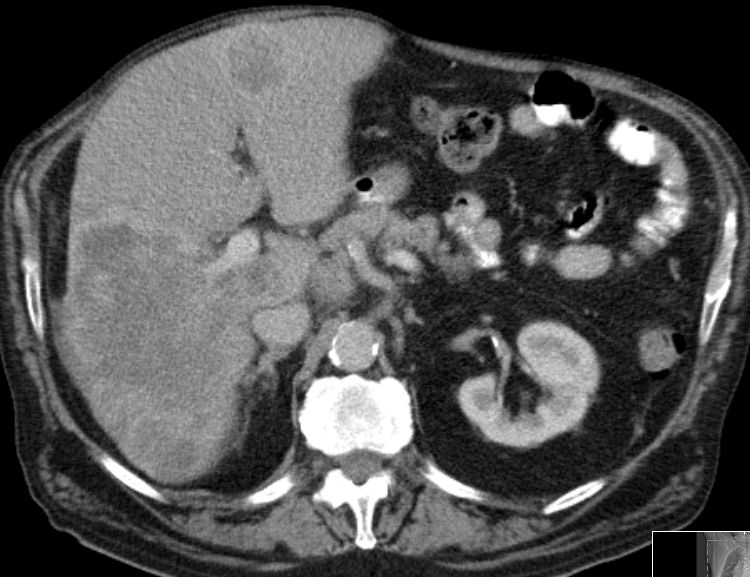

| CT | 61-jähriger trockener Alkoholiker mit bekannter Leberzirrhose und Ascites.

Mehrere Raumforderungen in der Leber. AFP 84. Keine Tumorzellen im Ascites.![]() | ||